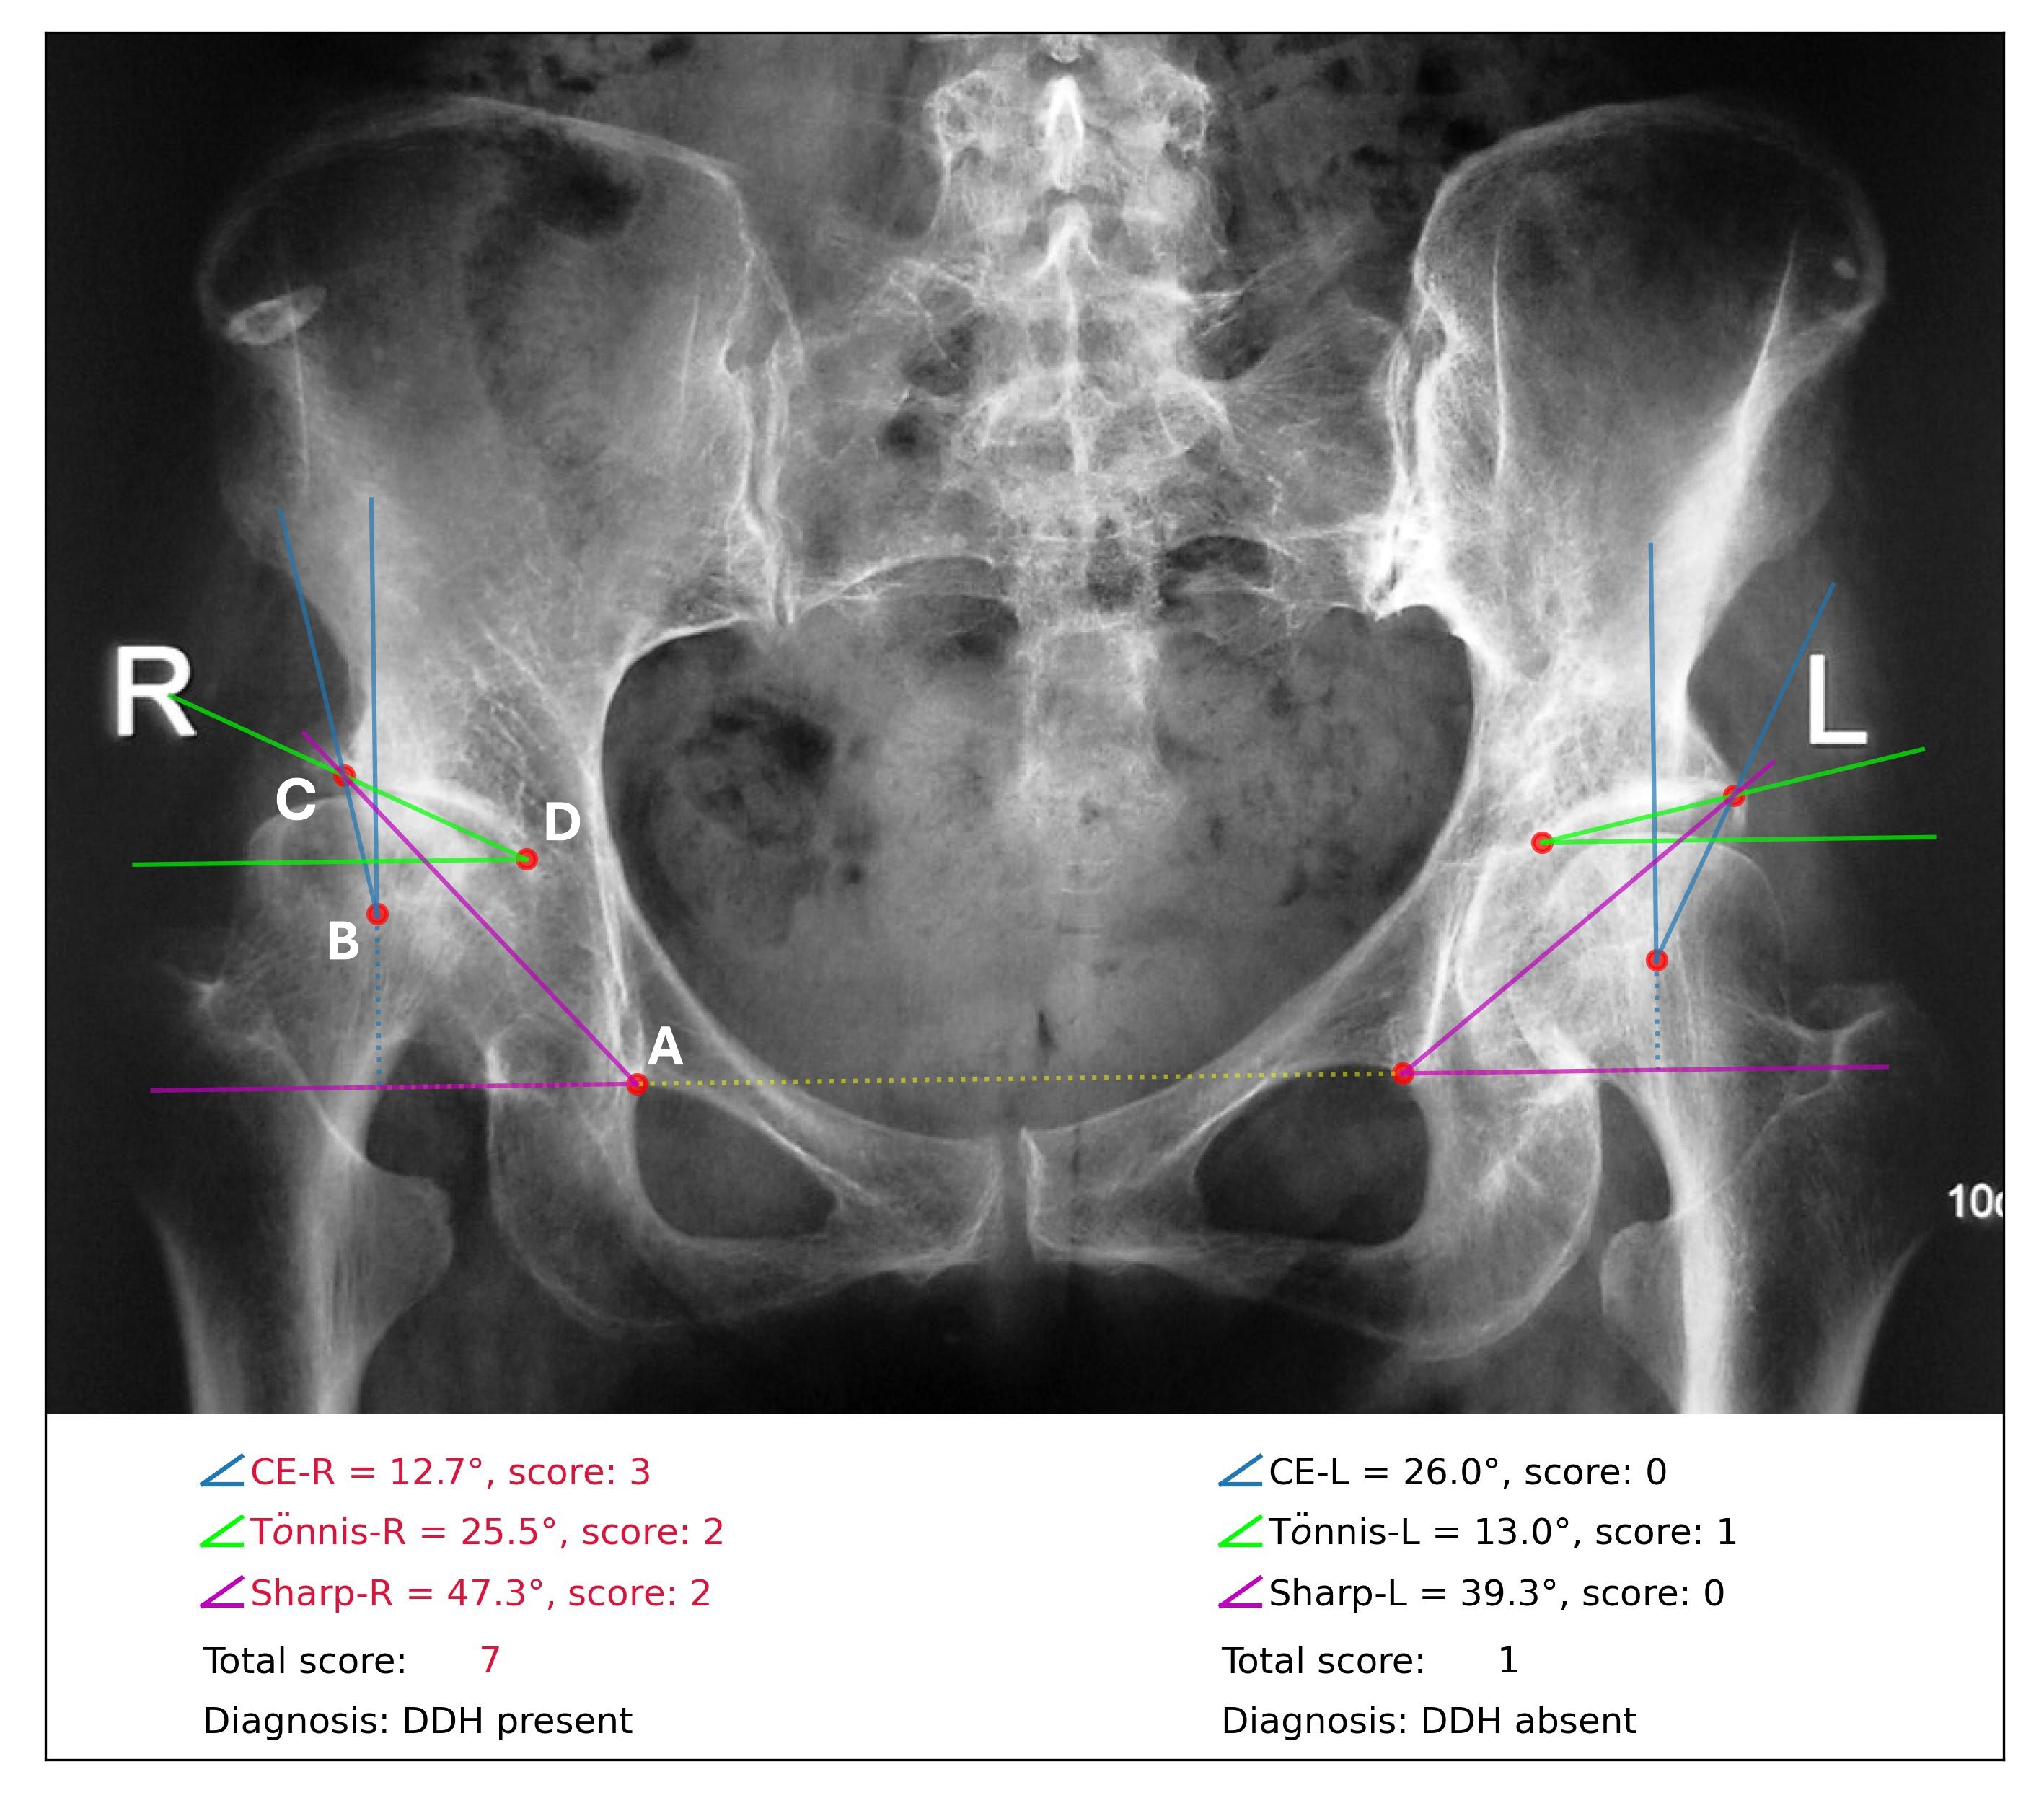

However, the accurate measurement of these diagnostic indices depends on the manual identification and assessment of key landmarks in radiographs, a process that can be inefficient and prone to errors, especially for less experienced clinicians. Consequently, diagnostic accuracy is often compromised by measurement variability and the quality of the radiographs [10]. Moreover, the subtle morphological differences between mild DDH and normal hips or other conditions can further complicate the diagnosis (see the minor difference between left and right hip shown in Figure 1), necessitating extensive training and clinical experience. To enhance diagnostic sensitivity, clinicians are suggested to comprehensively interpret the CE, Tönnis, and Sharp angles before making a diagnosis [7]\added[11], as these indices provide complementary insights into the condition. However, there is a lack of standardized and objective clinical guidelines for integrating those measurements into a definitive DDH diagnosis, highlighting the need for a reliable, interpretable, and automated diagnostic approach.

Refer to caption

Figure 1: Diagnosis generated by the proposed system based on an anteroposterior view pelvic radiograph. The system detects four keypoints on each side of the hip: (A) the inferior boundary of the teardrop point, (B) center of the femoral head, (C) lateral edge of the acetabulum, and (D) medial aspect of the acetabulum. The angle measurements and diagnostic scores are displayed in the bottom text (CE: Center–Edge). Angles that exceed the normal range are highlighted in red in the textual results. The right hip (marked as R on the radiograph) is diagnosed as “DDH present”, as the total score (7) is greater than the diagnostic threshold of 5. The diagnosis for the left hip (marked as L on the radiograph) is “DDH absent”.

In this study, we propose an end-to-end system for the comprehensive diagnosis of \addedadult DDH using anteroposterior view pelvic radiographs. Specifically, we developed a keypoint detection model based on the Mask-RCNN architecture to detect 8 keypoints on each pelvic radiograph. Subsequently, the CE, Tönnis, and Sharp angles are automatically measured according to the detected keypoints and their clinical definitions. To provide a more robust diagnosis, we introduced a new data-driven scoring system that integrates these angle measurements for a comprehensive assessment of DDH. Figure 1 illustrates an example of the visualized results generated by our system, showing a diagnosis of “DDH present” in the right hip and “DDH absent” in the left hip.

Following established clinical guidelines [5, 7, 8, 9, 11, 24], the radiological measurements in this study were defined as follows, referring to Figure 1. The Horizontal reference line (yellow dotted line) was defined as the line connecting the two teardrop points and passing through point A. The Vertical reference line (blue dotted line) was the vertical line perpendicular to the horizontal reference line and passing through point B. The Center-Edge (CE) angle was defined as the angle (blue) between the line connecting points B and C and the vertical reference line. The Tönnis angle was defined as the angle (green) between the line connecting points C and D and the line parallel to the horizontal reference line and passing through point D. Finally, the Sharp angle was defined as the angle (purple) between the line connecting points A and C and the horizontal reference line. The ground truth measurement of CE, Tönnis, and Sharp angles were calculated based on the ground truth keypoint locations and these defined measurement criteria.